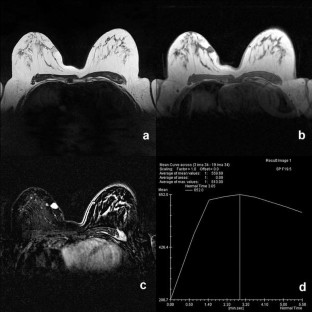

Dermatofibrosarcoma protuberans (DFSP) of the breast is a rare malignant tumor, and its preoperative diagnosis is extremely difficult. Local recurrence of DFSP is frequent after incomplete resection because of either false diagnosis or inadequate standard surgical excision. We present a case of DFSP that showed disconcordant results using different imaging modalities, suggesting that the MRI finding of subcutaneously located highly vascular tumor with suspicious kinetics but together with negative Cho peak on (1H) MRS, might be suggestive of the diagnosis of DFSP.